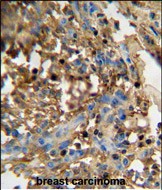

分类: 科研抗体货号: P30872别名: EF-hand domain-containing family member B, EFHB应用: WB,IHC,FCM反应种属: Human